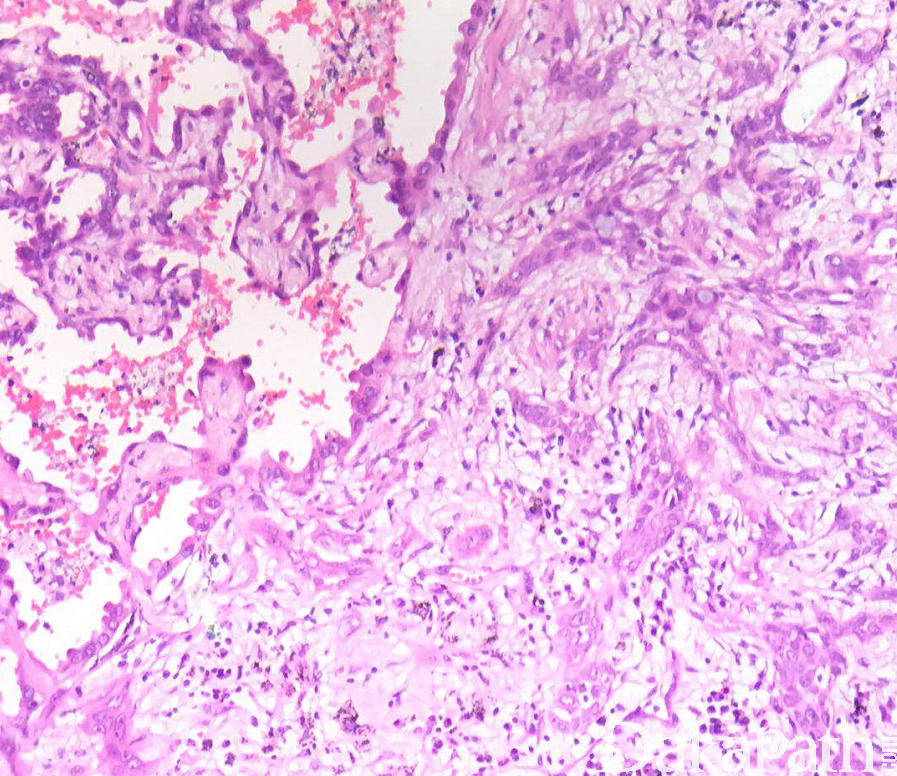

同时具有鳞状细胞癌和腺癌两种成分的癌,其中每种成分至少占全部肿瘤的 10%;两种成分可能相互分开、相邻或混合存在;

鳞状细胞癌显示明确的角化或细胞间桥,腺癌显示腺泡、小管或乳头状结构;